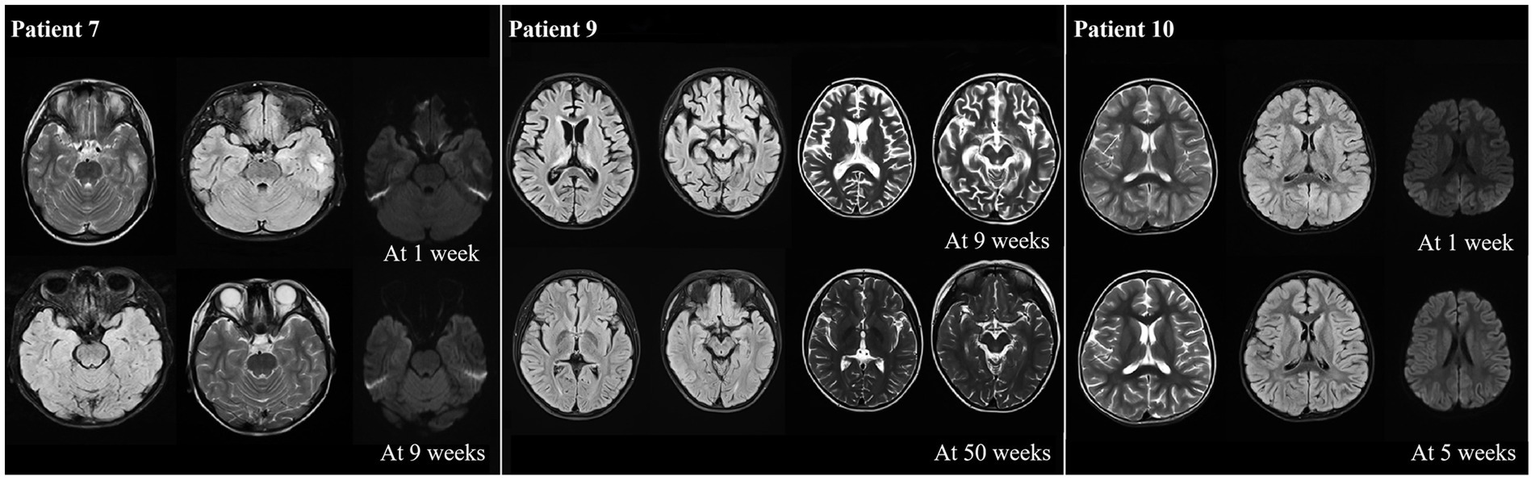

The MRI results showed that most of the patients (10/13) exhibiting different abnormalities (Table 1). An abnormal signal appeared in the bilateral frontal lobe and left temporal lobe cortex, and subcortex of P7 at one week after onset. The left temporal cortex and subcortical abnormal signal range were significantly reduced at 9 weeks after onset compared with onset. P9 presented with bilateral thalamus and right hippocampus on admission, with the possibility of viral encephalitis. The cerebral sulcus fissure was slightly broader and deeper, and the bilateral lateral ventricles were slightly enlarged at 9 weeks after the disease onset (following immunotherapy with methylprednisolone). The abnormal signal was absorbed, and the sulcus fissure and bilateral ventricle were slightly less at 50 weeks after onset than at 9 weeks after onset. P10 had multiple T2 abnormal signals in the head of the bilateral caudate nucleus, bilateral frontotemporal parietal, and occipital cortex at one week after onset. FLAIR showed hyperintensity, and limited diffusion. Most lesions in the head of the bilateral caudate nucleus, bilateral frontotemporal parietal-occipital cortex and diffusion-limited lesions were smaller at 5 weeks after onset than at one week after onset (Figure 5).

Figure 5

Abnormal neuroimaging findings in patients with anti-CASPR2 Ab-related encephalitis. Patient 7 with abnormal signalin bilateral frontal left temporal cortex and subcortical at one week after disease onset. Compared with onset, the left temporal cortex and subcortical signals were significantly reduced at 9 weeks after onset; the neuroimaging of P9 revealed bilateral thalamus, brain foot small sheet of abnormal signal, brain groove fissure slightly wide and deep, bilateral lateral ventricle slightly enlarged at 9 weeks from oneset, all symptoms improved at 50 weeks from oneset; the neuroimaging of P10 displayed bilateral caudate head, multiple T2 abnormalities in bilateral frontal, temporal and occipital cortex, FLAIR hyperintensity, and limited diffusion at one week after onset. After 5 weeks of treatment, all lesions decreased compared to one week of onset. CASPR2, Contactin-Associated Protein-like 2; Ab, antibody; MRI, Magnetic Resonance Imaging; FLAIR, fluid attenuated inversion recovery.